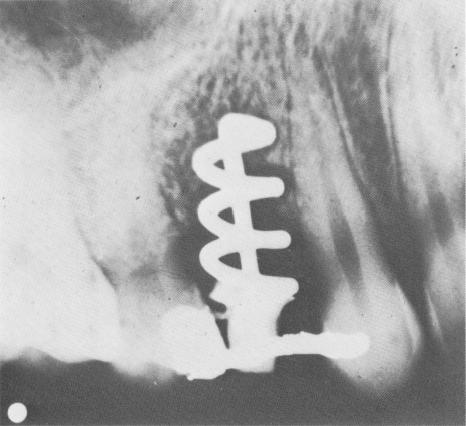

В 40-е годы «отец современной имплантологии» Формиджини (Formiggini) и Зеппони (Zepponi) разработали эндооссальный имплантат в форме спирали из нержавеющей стали, допускающий срастание кости и металла. Доктор Перрон Андрес (Perron Andres) из Испании модифицировал спиралевидную конструкцию зубного протеза Формиджини, включив в нее сплошной вал.

Спираль Формиджини